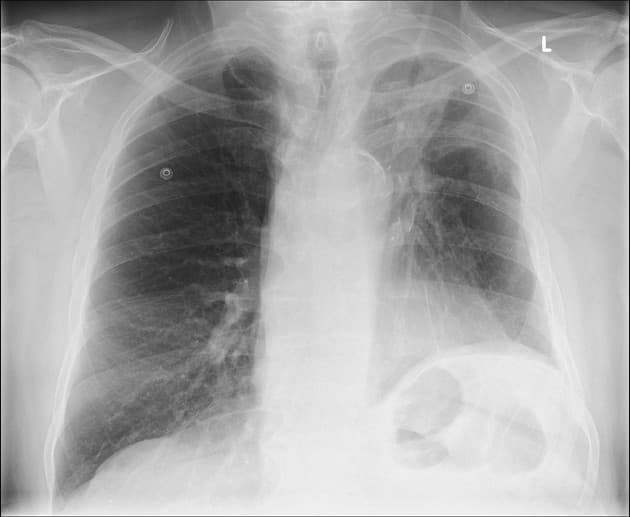

A lobectomy is a surgical procedure that involves the removal of one of the lobes of the lung. The procedure begins with a preoperative evaluation to ensure the patient is a suitable candidate for surgery. This evaluation typically includes imaging studies such as CT scans or PET scans, pulmonary function tests, and blood work. On the day of the surgery, the patient is given general anesthesia to ensure they remain unconscious and pain-free throughout the procedure. Depending on the surgical approach, the surgeon may perform either an open thoracotomy or a minimally invasive technique such as Video-Assisted Thoracoscopic Surgery (VATS) or Robot-Assisted Thoracoscopic Surgery (RATS).

For an open thoracotomy, the surgeon makes a large incision in the chest to access the lung. For minimally invasive techniques, smaller incisions are made, and specialized instruments, along with a camera, are used to visualize and perform the surgery. Once the lung is accessed, the surgeon identifies the lobe that needs to be removed. They carefully dissect the pulmonary artery, pulmonary vein, and bronchus associated with the lobe, ensuring that these structures are securely ligated and divided. This step is crucial to prevent bleeding and maintain the integrity of the remaining lung tissue.